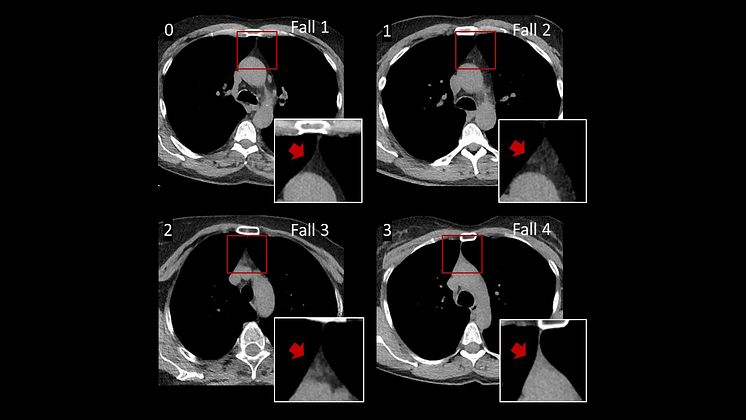

Thymusvävnad är ljus medan fettvävnad är mörk vid datortomografi. Här ses olika grader av fettomvandling av thymus, från helt fettomvandlad (0) till mestadels bevarad thymusvävnad (3).